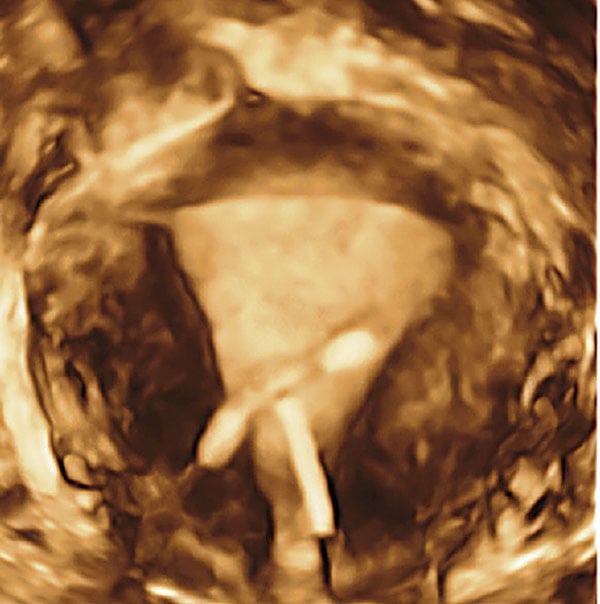

Coronal view, reconstructed from 3-D ultrasound, reveals an incorrectly positioned IUD. Image courtesy of American Journal of Obstetrics and Gynecology

"Doing a CT scan first for female patients with lower abdominal pain is dangerous, wasteful and expensive," said Benacerraf in a prepared statement. The clinical professor in obstetrics, gynecology, reproductive biology and radiology at Harvard Medical School and Brigham and Women's Hospital, went on to say, "We must educate the medical community to consider adopting 3-D ultrasound as the first assessment tool for specific gynecologic indications, such as evaluating the uterus for Mí¼llerian anomalies or localization of IUDs or other intracavitary lesions."

A decade ago 3-D ultrasound was more clinical curiosity than tool, limited by its dependence on the skill of the operator and restricted primarily to fetal assessment. Since then, however, volumetric scanning has matured. Its automated acquisition of operator-selected volumes can be sliced into hundreds of images reconstructed at just about any angle. Ultrasound is less expensive and less time-consuming than MRI, and free from the ionizing radiation of CT. And yet it provides many of the answers that these two modalities cannot.